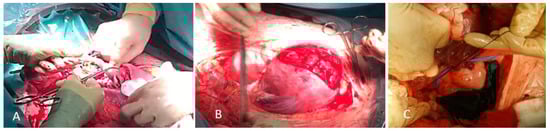

2. Case Report